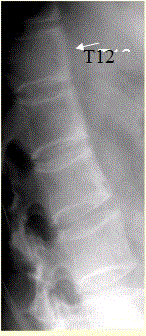

问题 患者男,35岁,外伤后行腰椎CR检查,结果如下图。 强直性脊柱炎的主要病理改变为

选项 A.附丽病 B.滑膜炎 C.关节囊、韧带附着处纤维软骨增生肥大、骨赘形成 D.大量新生骨形成和骨旁骨化 E.广泛滑膜增生伴出血、含铁血黄素沉积 F.异位骨化或钙化

答案 AB